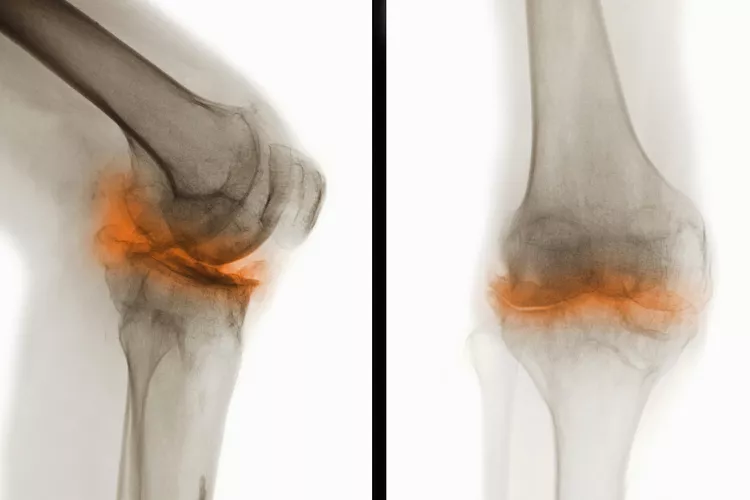

骨關節(jié)炎(Osteoarthritis, OA),一種常見的慢性關節(jié)疾病,主要特征是關節(jié)軟骨退化和關節(jié)邊緣骨質增生。隨著病情進展,骨關節(jié)炎不僅會導致關節(jié)疼痛和功能受限,還可能引發(fā)一系列并發(fā)癥,影響患者的整體健康和生活質量。

在骨關節(jié)炎(OA) 中,覆蓋骨頭末端并幫助骨頭相互滑動的光滑軟骨會逐漸磨損。這會導致骨頭相互摩擦和磨擦。

年齡、受傷和重復運動都可能導致骨關節(jié)炎,但最常見的原因是正常的磨損,尤其是在50歲以后。它可以發(fā)生在任何關節(jié)上,但最常見于手、膝蓋、臀部和脊柱。

骨關節(jié)炎是一種慢性疾病。骨關節(jié)炎無法治愈。一旦軟骨破裂,它就不會自行再生。隨著時間的推移,您可能會因患有骨關節(jié)炎而出現其他問題或并發(fā)癥。